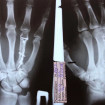

а также при переломах, в том числе для установки

металлических фиксирующих конструкций или их удаления.